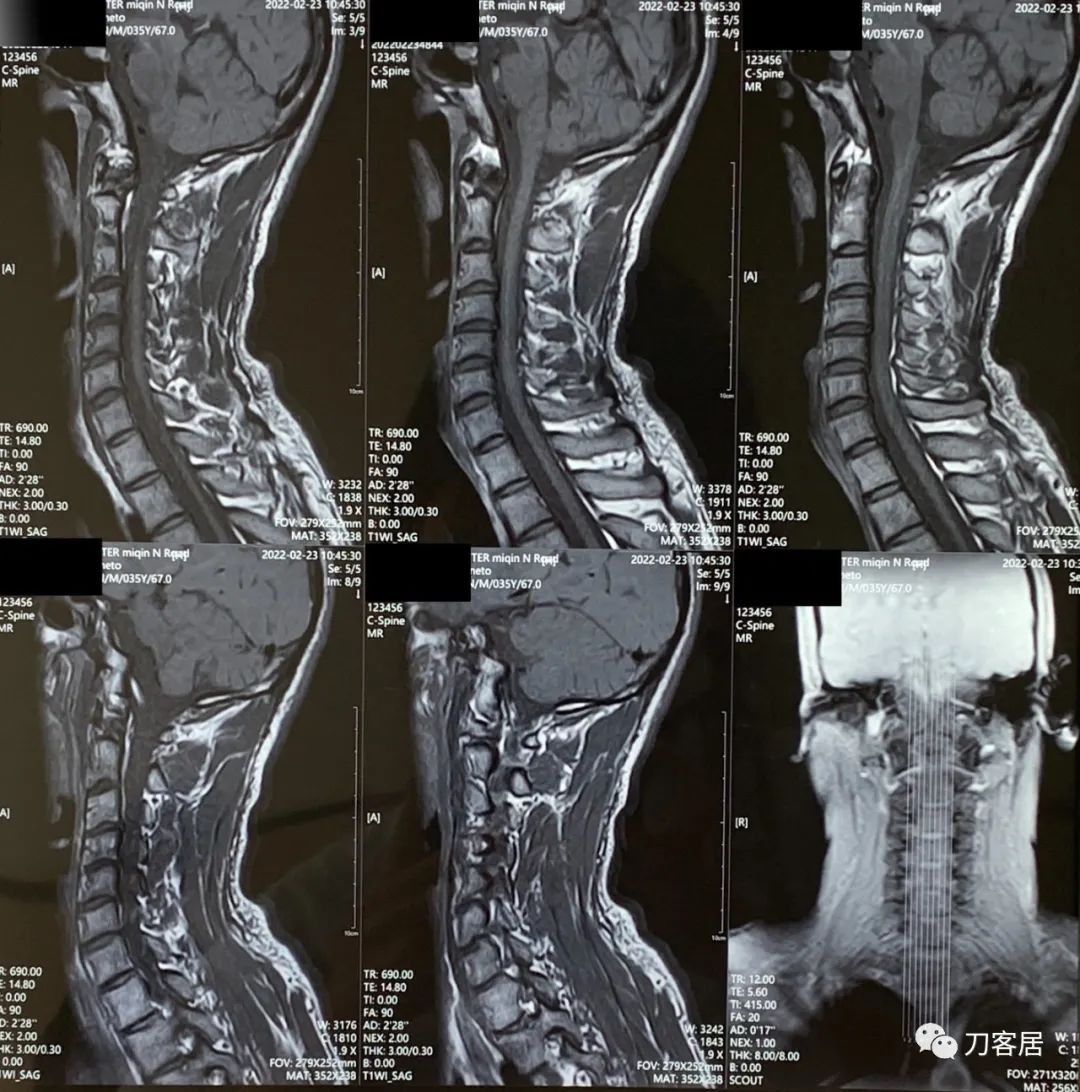

然后建议患者做颈椎和胸椎的MRI检查,看看有无脊髓受压表现。

颈椎及胸椎MRI检查后,并没有发现颈椎管及胸椎管有椎间盘突出,也没有椎管狭窄及脊髓受压。

图6. 20220223胸椎MRI01

图7. 20220223胸椎MRI02

图8. 20220223颈椎胸椎MRI报告

所以考虑该患者应该是脊髓本身出问题了,可能是脊髓炎,也可能是脊髓本身我并不知道的其他疾病,导致出现了上位神经元损害的表现。然后建议患者去神经内科会诊。